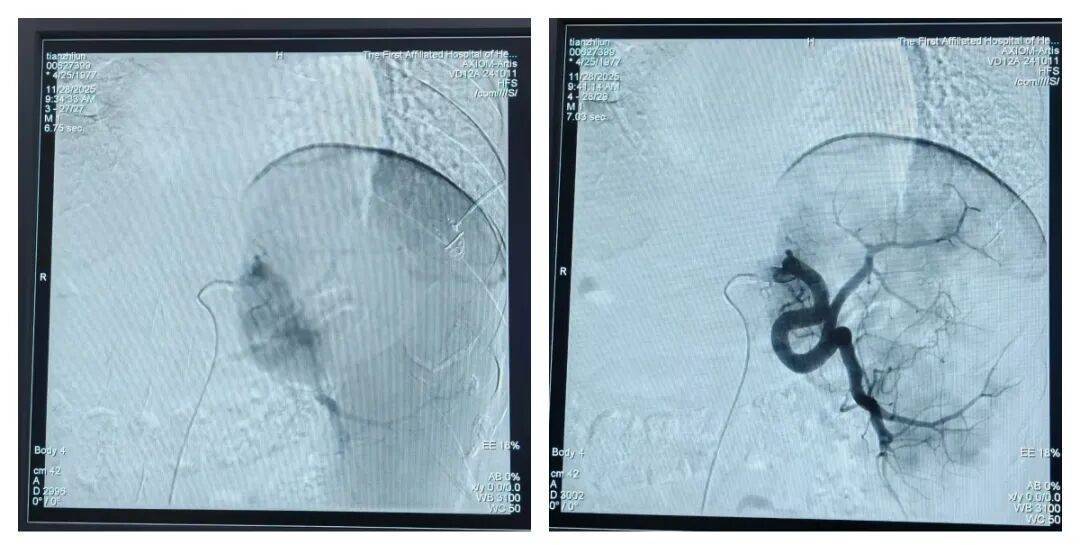

△术前脾亢、脾外带广泛显影与术后脾外带2-3cm显影消失的对比